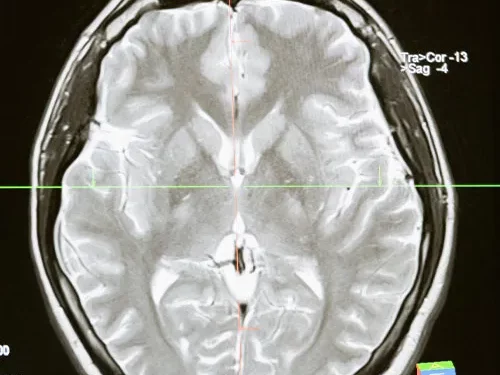

Cirugía Neurológica

Radiocirugía/Columna

Contamos con un programa de tratamiento para tumores del cerebro “Cirugía sin Bisturí” que se realiza con equipos de alta tecnología llamados aceleradores lineales en los hospitales de mayor infraestructura de la Ciudad de México.